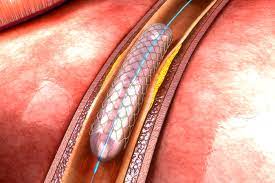

Arteriële Hervaskularisasie

Pasiënte met arteriële inkorting, wat nie na wense reageer op basiese wondsorg of gevorderde wondsorg nie, kan oorweeg word vir arteriële prosedures. Dr Weir is ’n Vaskulêre Chirurg en sal die opsies met die pasiënt bespreek en op die beste ingreep vir die spesifieke pasiënt, saam met die pasiënt besluit